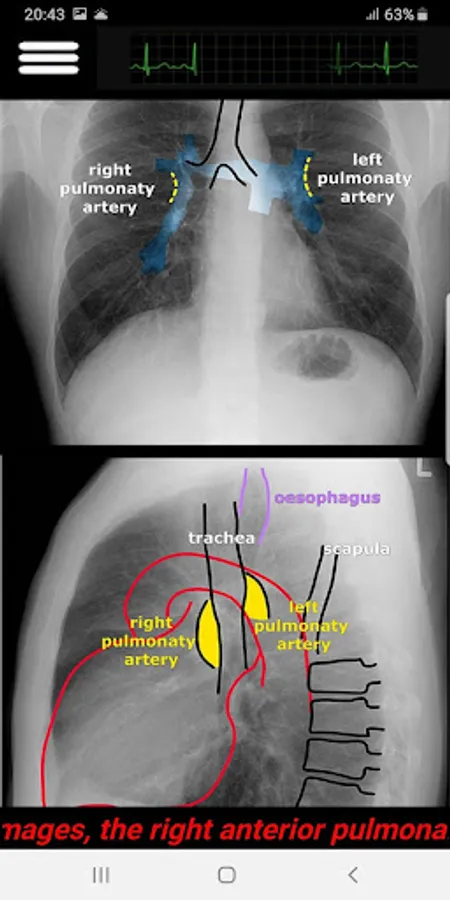

In brief, This application designed to have a quick review and interpret a Chest X-Ray in your daily practice. It covers the normal and most abnormal Chest X-Rays in an organized way to approach. It is recommended app for all ER doctors, general practitioners, Medical Students and who is interested.